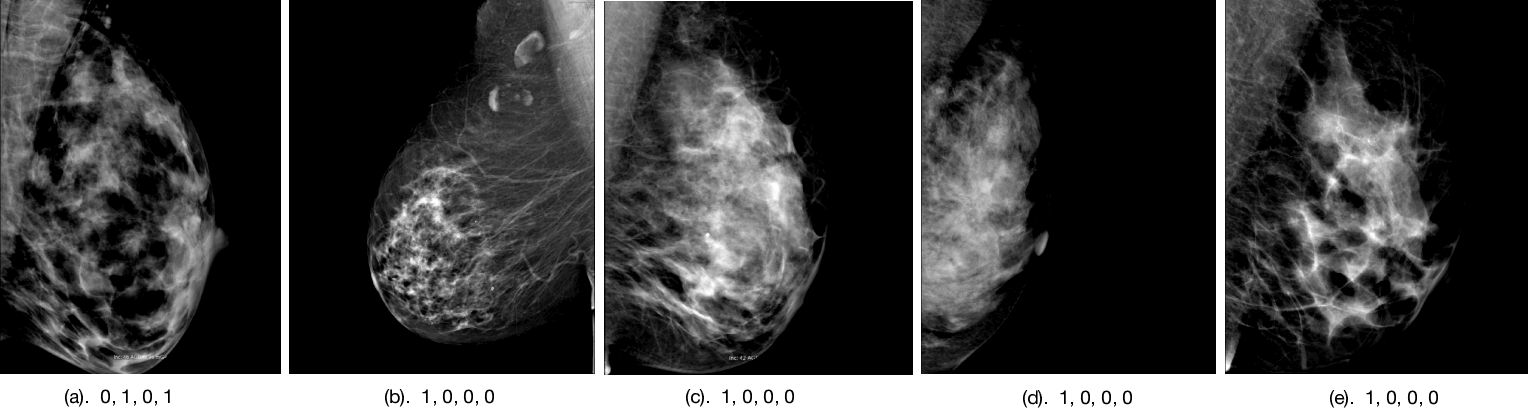

The mammogram input data. The mammography dataset contains 220 unilateral full-field digital mammograms obtained from 110 unique patients at Brigham and Women’s Hospital. These images fall into three classes: no malignancy (110 images), malignancy (66 images), or contralateral to the breast with a malignancy (44 images). All code and the dataset for this paper are on Github: https://gistmammocnn.github.io/.

Figures 4, 5, and 6 show the imaging for which both humans and CNNs make mistakes, model introduced errors, and model corrected human errors. Figure 7 shows the receiver operating characteristic curve (ROC curve) for each of the 16 end-to-end models between the CNNs and radiologist gist plus CNNs. Tables 1 and 2 show the AUC data and differences used in the main text from the 16 conditions we have tested. Although the present work provides knowledge about adding radiologists’ data into CNN, it does not allow for training on new data, thus restricting our application domain to a small range of in-house data.